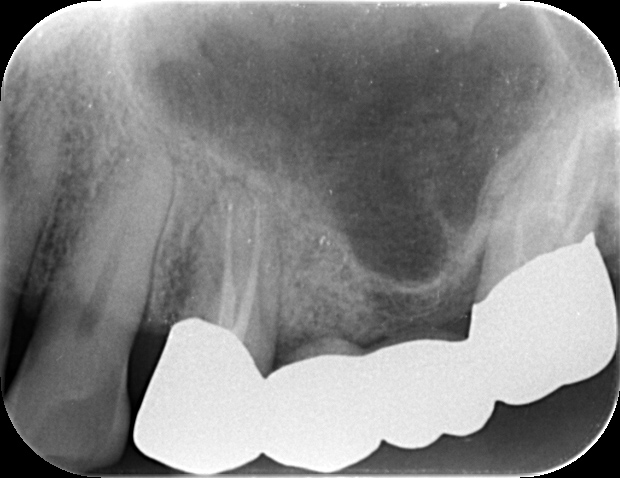

根管治療を行った歯が痛み、周囲が腫れている場合は、歯の根が割れていることがあります。神経を失った歯は脆くなり、何かの拍子で割れやすくなるのです。割れてしまった歯は多くの場合、抜歯が必要になりますが、状態によっては「破折歯牙再植」という術式で治療できることがあります。破折歯牙再植では、割れた歯を一度抜歯し、強力な接着剤で修復してから元の位置に埋め直します。

この方法で治療した歯は数ヶ月で安定し、ご自身の歯なのでインプラントなどに比べてもしっかりした噛み心地が保たれます。